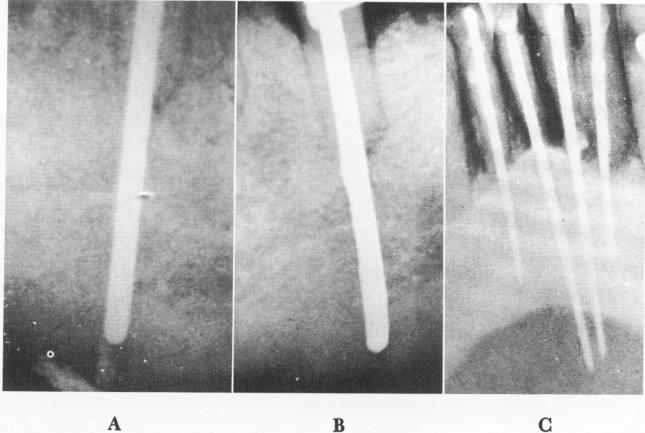

Fig. 13-62. Overshooting accidents. A, The post overshot a lower premolar and went through the jaw. It was immediately withdrawn into the bone and this radiograph taken. B, Five weeks later. C, In this case, overshooting was detected only after cementation. Radiograph taken 1 year after the operation. (From Orlay, H. G.: Endodontic implants, J. Oral Implant Transplant Surg., pp. 44-53, 1965.)

1 Post overshot lower premolar & went through jaw, immediately withdrawn